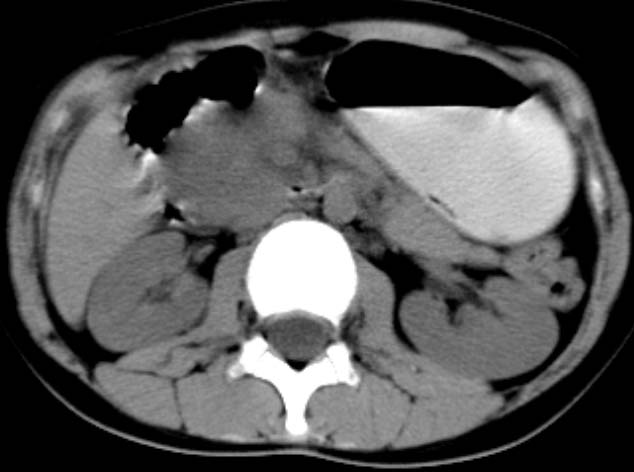

女,14岁。腹痛3天。腹部触诊未触及包块。碘剂阳性未增强。求助战友。。。。。。。。。。。

1)急性胰腺炎。2)肝右叶后上段肝内胆管结石。3)左侧输尿管上段扩张,原因待查。

是不是胰腺炎结合几项化验指标确诊不是问题,我觉着下腹部及盆腔应观察一下。

化验结果:血.尿淀粉酶正常。

既然实验室检查不支持炎症,那就强化或mr检查帮助明确吧.

支持:急性胰腺炎!血.尿淀粉酶正常那么mri检查一下。

病灶应在胰头下区,不一定是胰头,结合周边低密度水肿,是否可能为十二指肠(xi)室炎症或其它炎症。

胰周无明显渗出,吉氏筋膜未见增厚。血尿试验室检查不支持。排除胰腺炎。